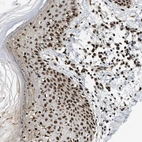

Immunohistochemical staining of human skin shows strong nuclear positivity in squamous epithelial cells.